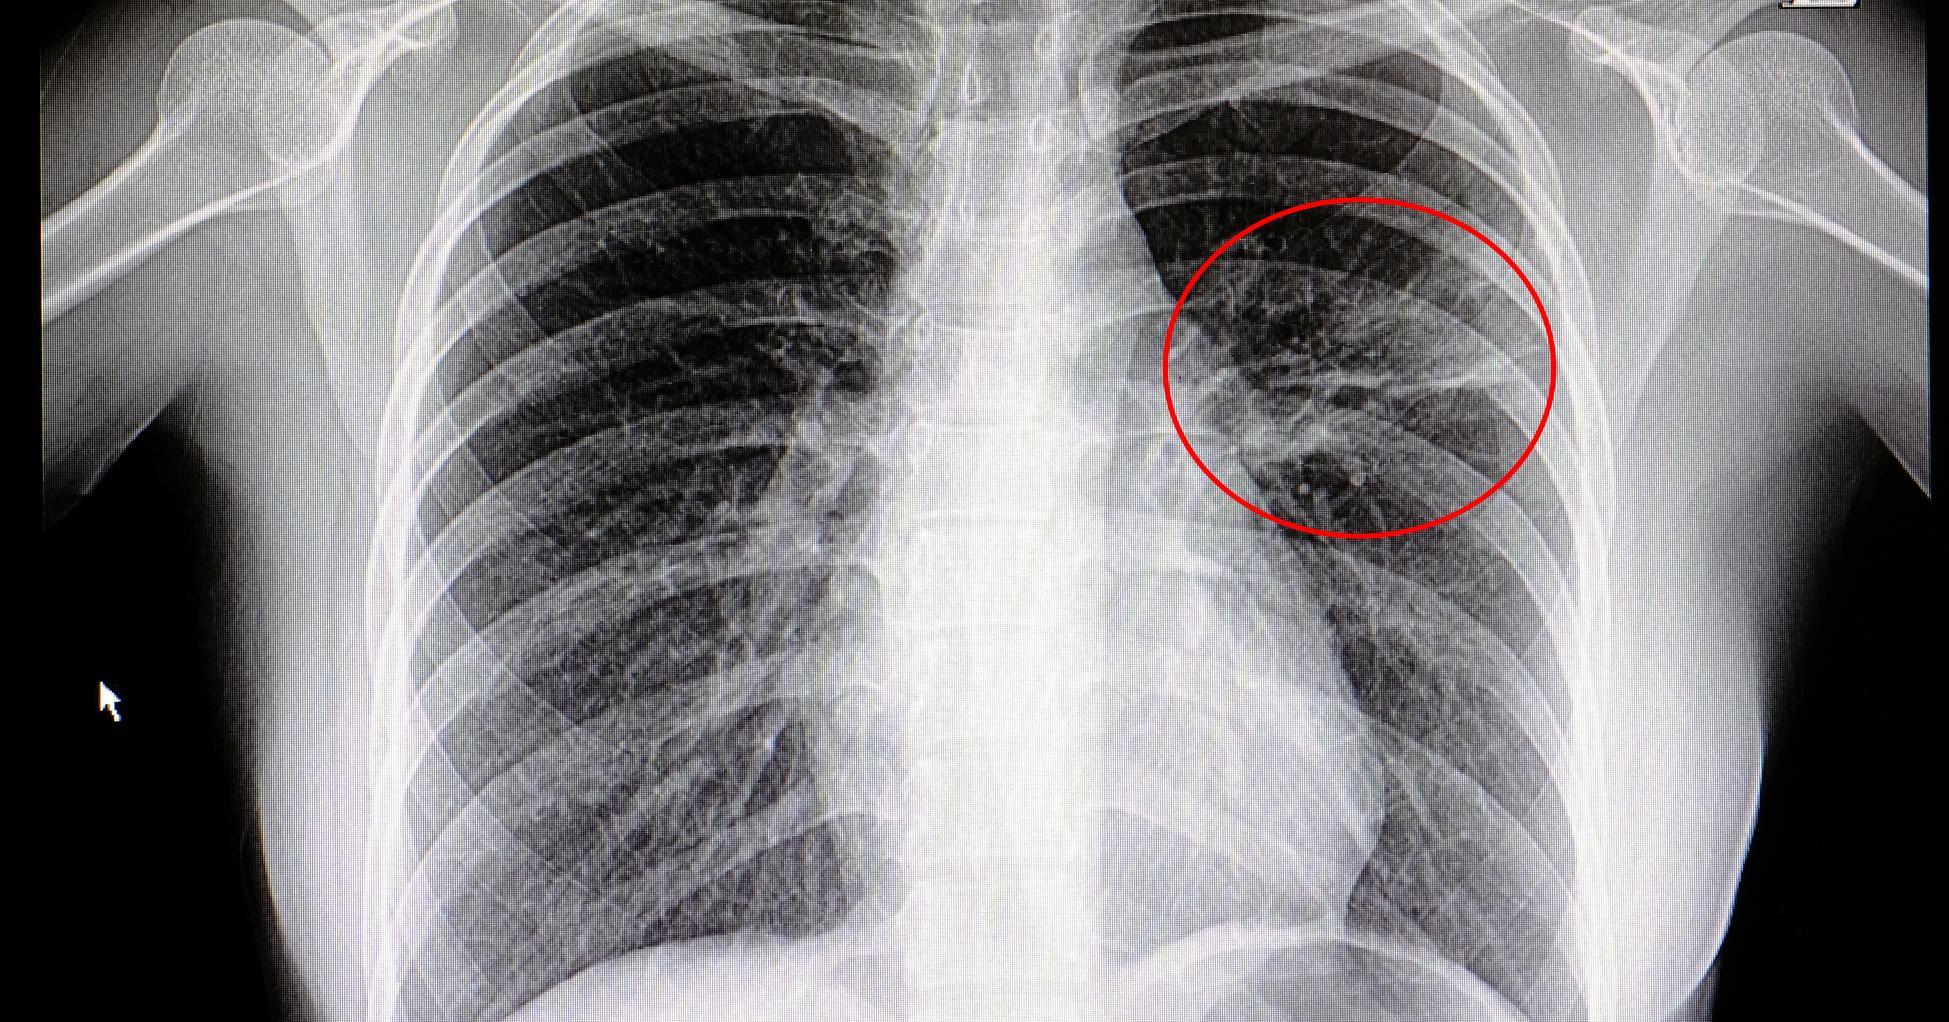

Acute Pulmonary Edema

Many of the causes on this list lead to the development of respiratory acidosis because they adversely affect the lungs' ability to properly remove carbon dioxide. Any condition or disease that affects an individual's breathing can also heighten their risk of respiratory acidosis. A common cause of this condition is acute pulmonary edema, which occurs when there's an excess amount of fluid in the lungs. This fluid develops within the various air sacs located around the lungs, which is what causes the breathing issues and makes it very difficult for the lungs to remove carbon dioxide, which is a problem that will eventually lead to respiratory acidosis. This can result from serious infections, heart problems, and trauma to the chest wall. Getting early treatment for acute pulmonary edema will substantially lessen an individual's risk of suffering from a severe health problem. The symptoms associated with acute pulmonary edema include irregular heartbeat, wheezing, anxiety, feelings of suffocation, and severe shortness of breath.